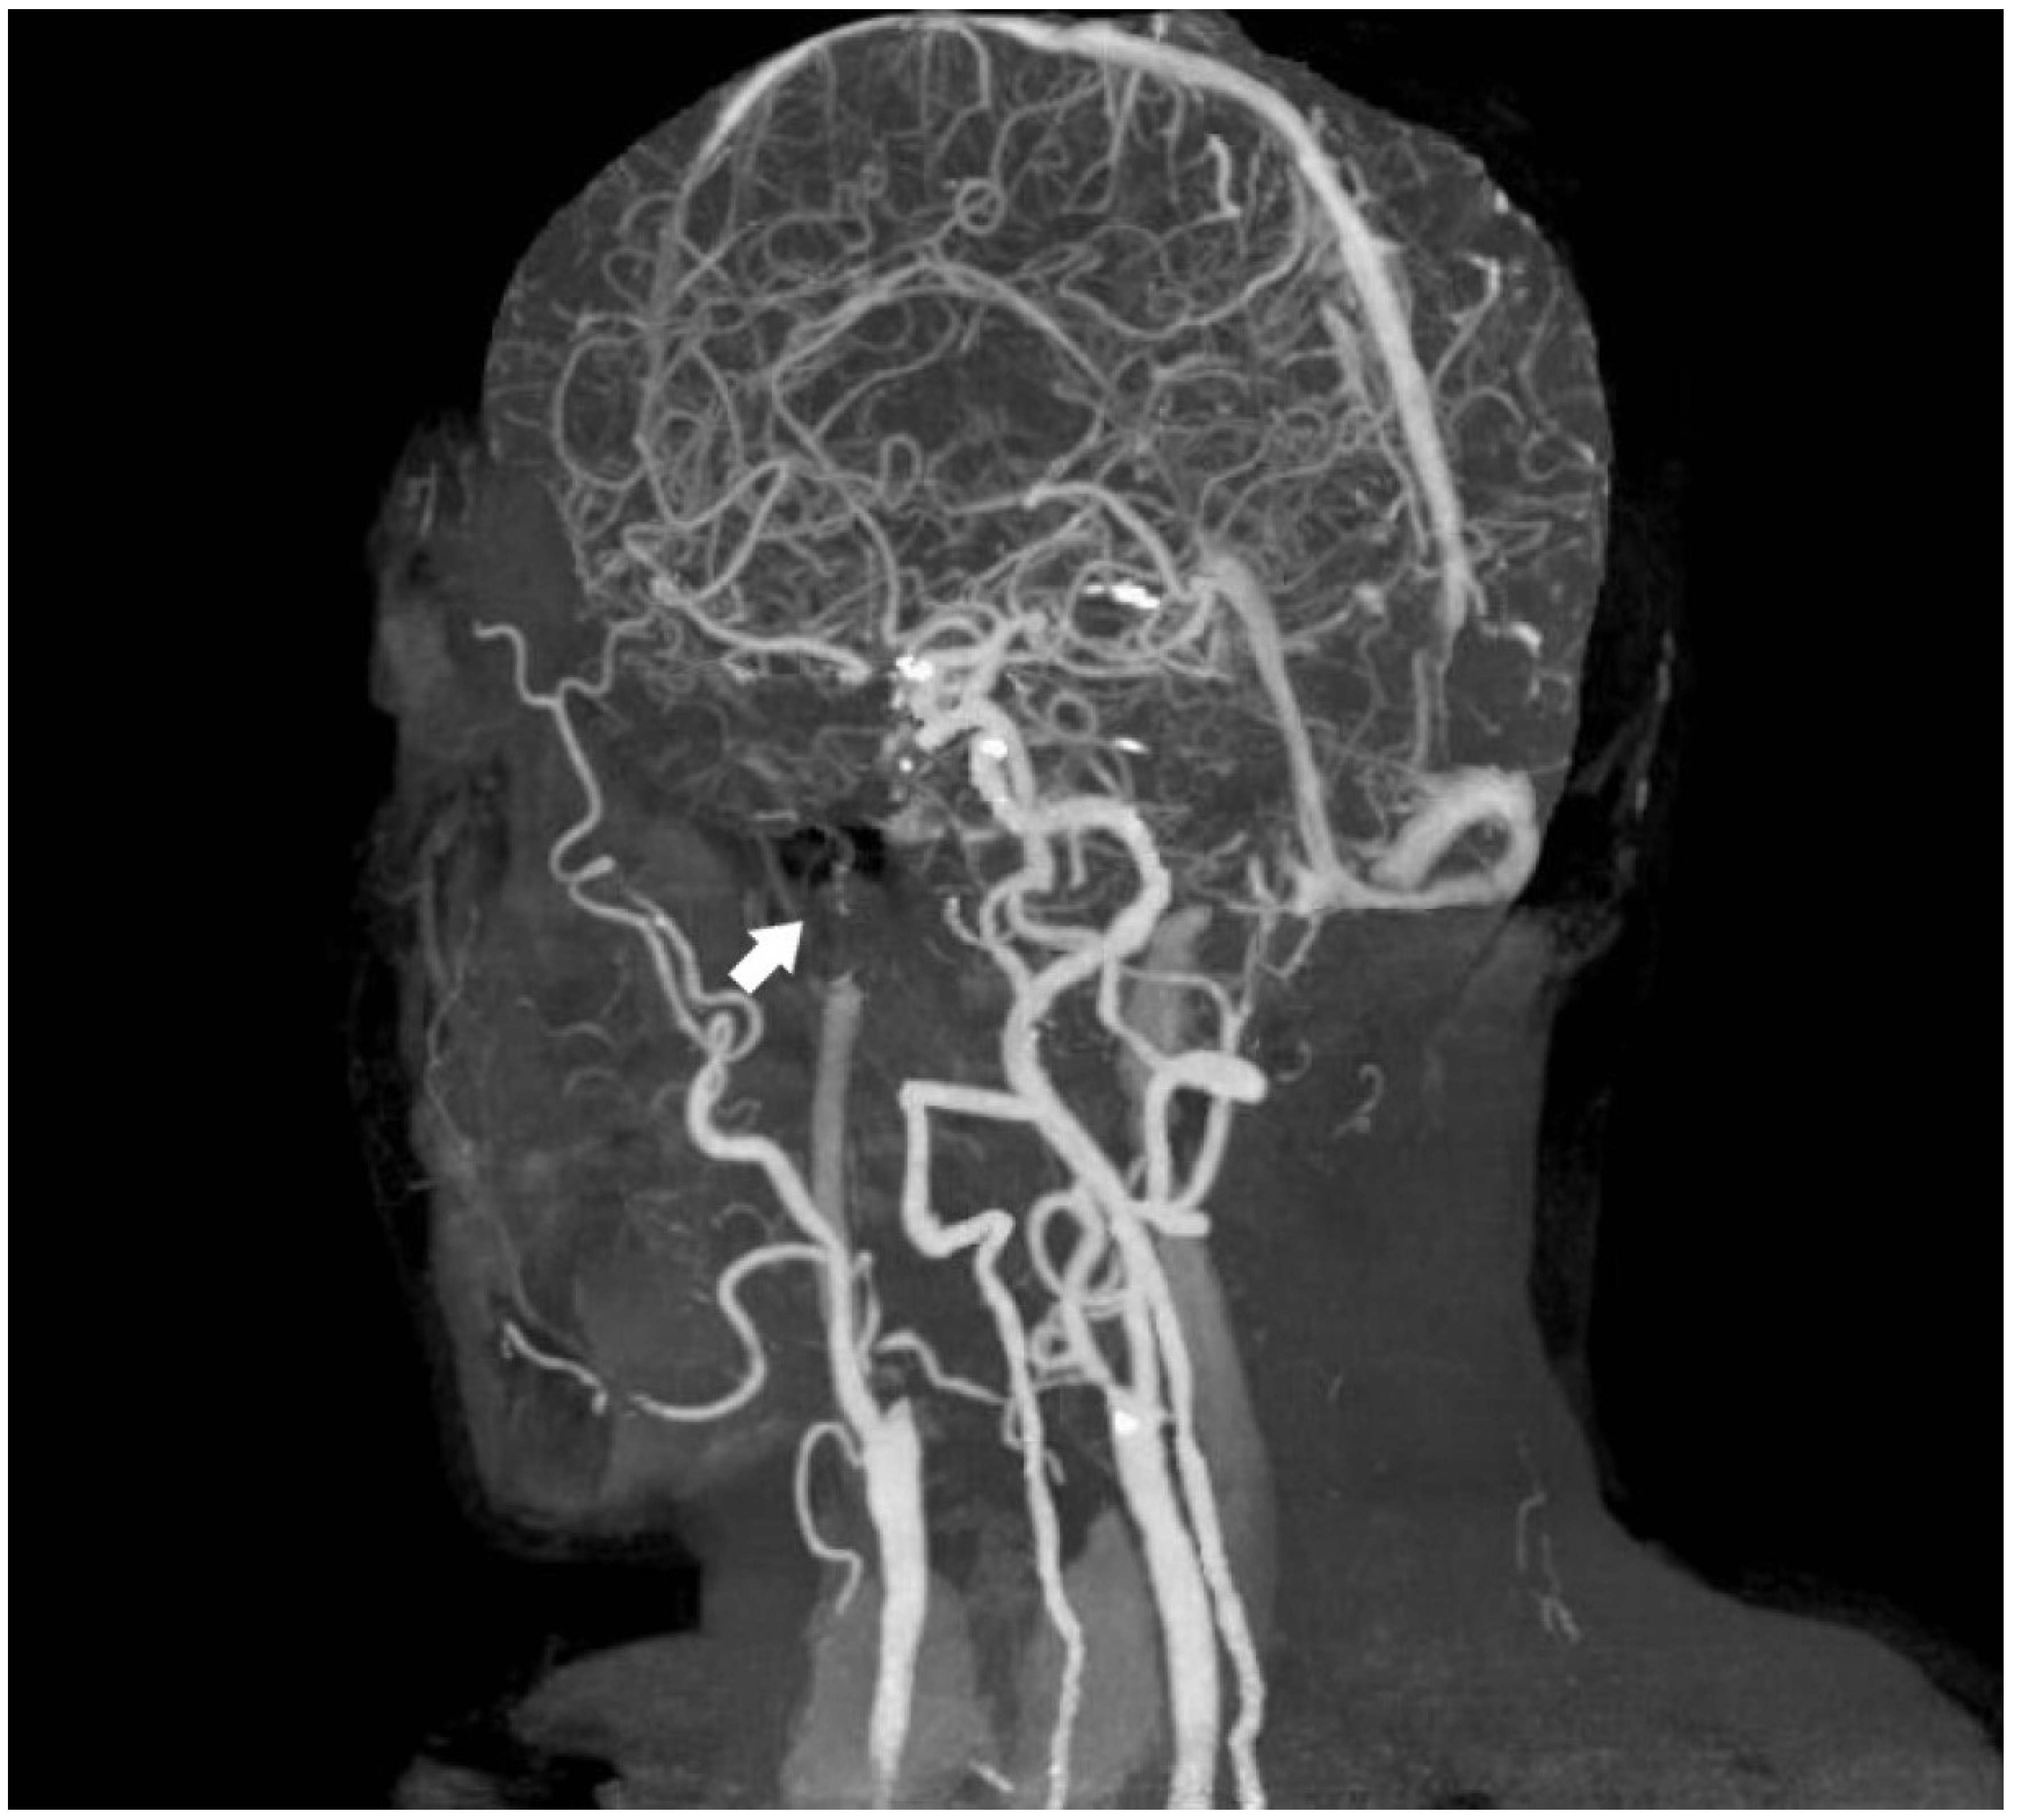

A review of the patient’s radiologic records revealed a cranial CT angiography performed nine years ago. Imaging showed no contrast in the left internal carotid artery. In addition, the left petrosal carotid canal was found to be intact (Figure 5 and Figure 6).

Figure 5.

CTA image obtained from the patient nine years ago [White arrow: indicates a filling defect beginning at the proximal segment of the ICA].